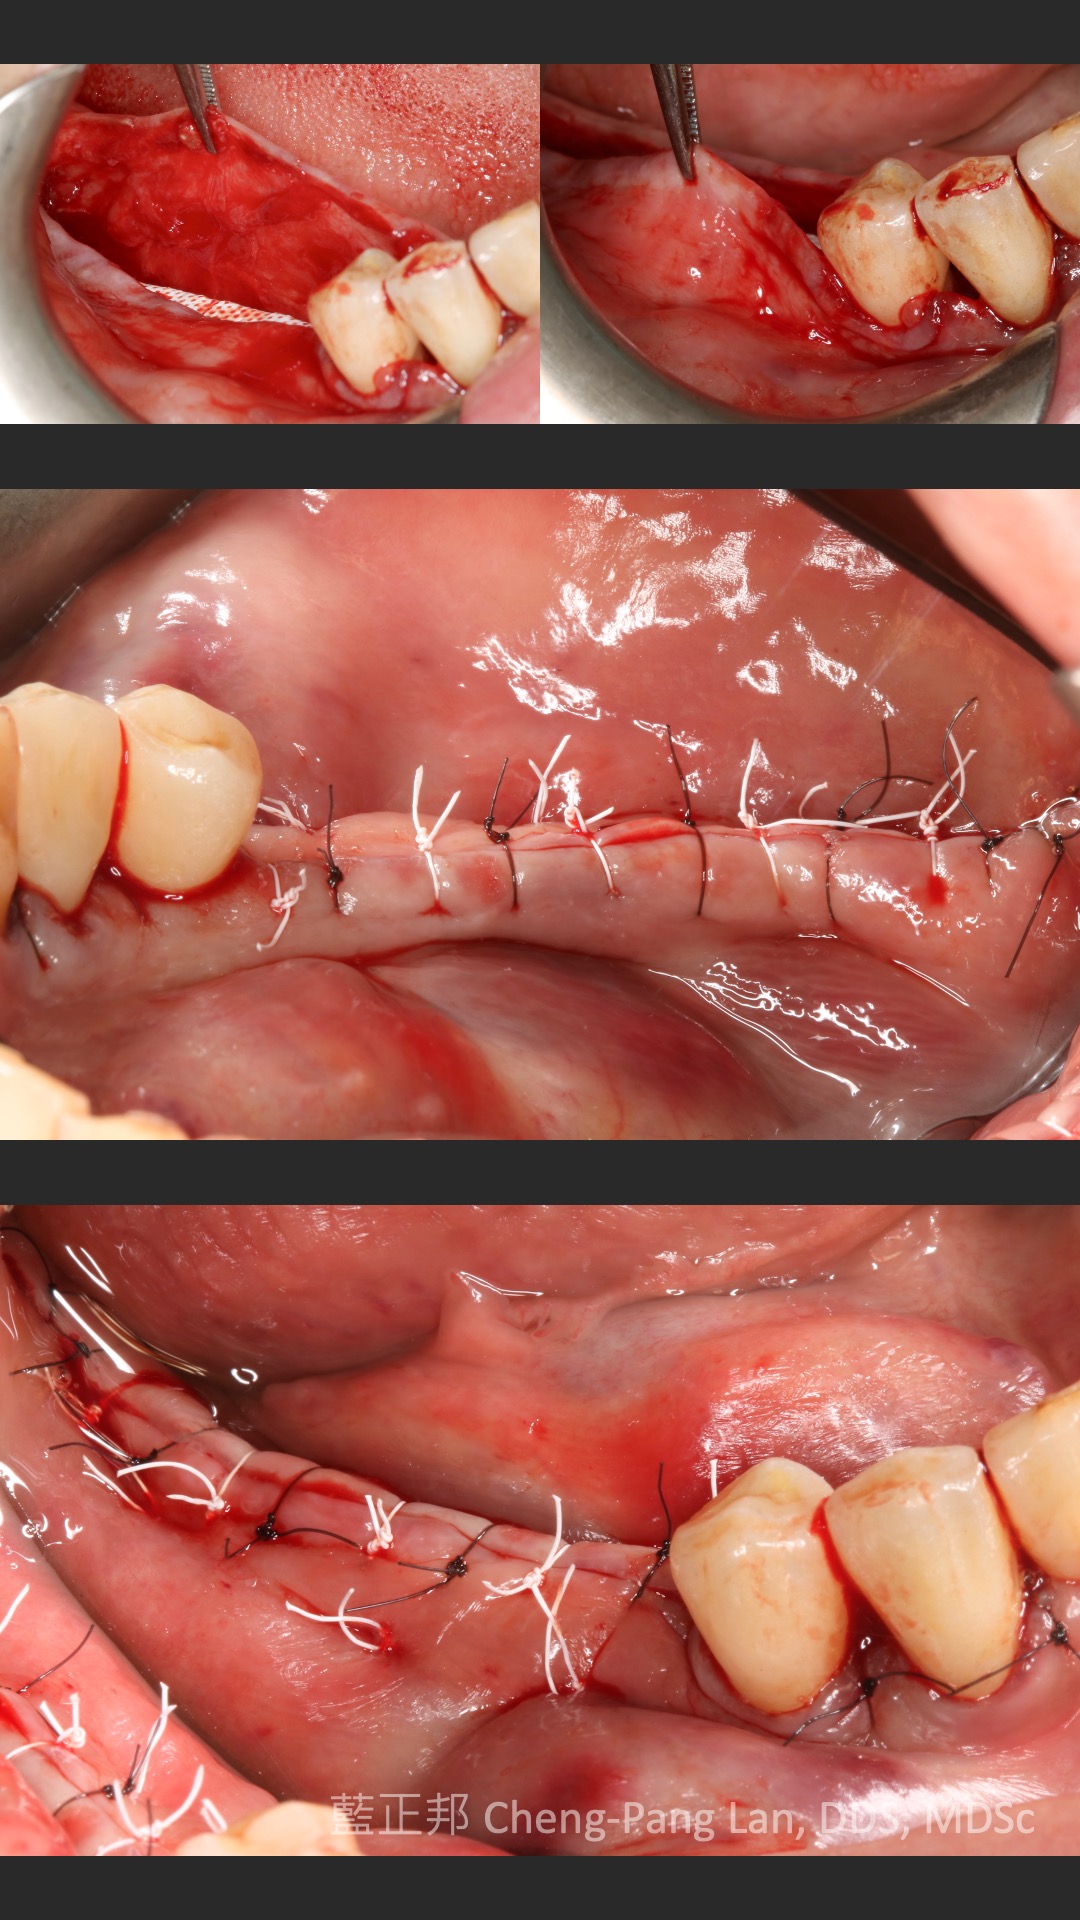

●第十一章垂直補骨,前一版的作者Massimo Simion,改成了Istvan Urban,果如我2016年判斷的,Istvan Urban已成為垂直補骨的接班人,連主編Buser也這麼認為(笑)。這邊寫的是簡易版,若朋友有興趣詳細的垂直補骨,直接看Urban寫的兩本垂直補骨書即可,我這邊也有第二本Vertical 2心得。但是十一章關於頰側與舌側的皮瓣鬆弛,寫得簡潔扼要,值得詳讀。